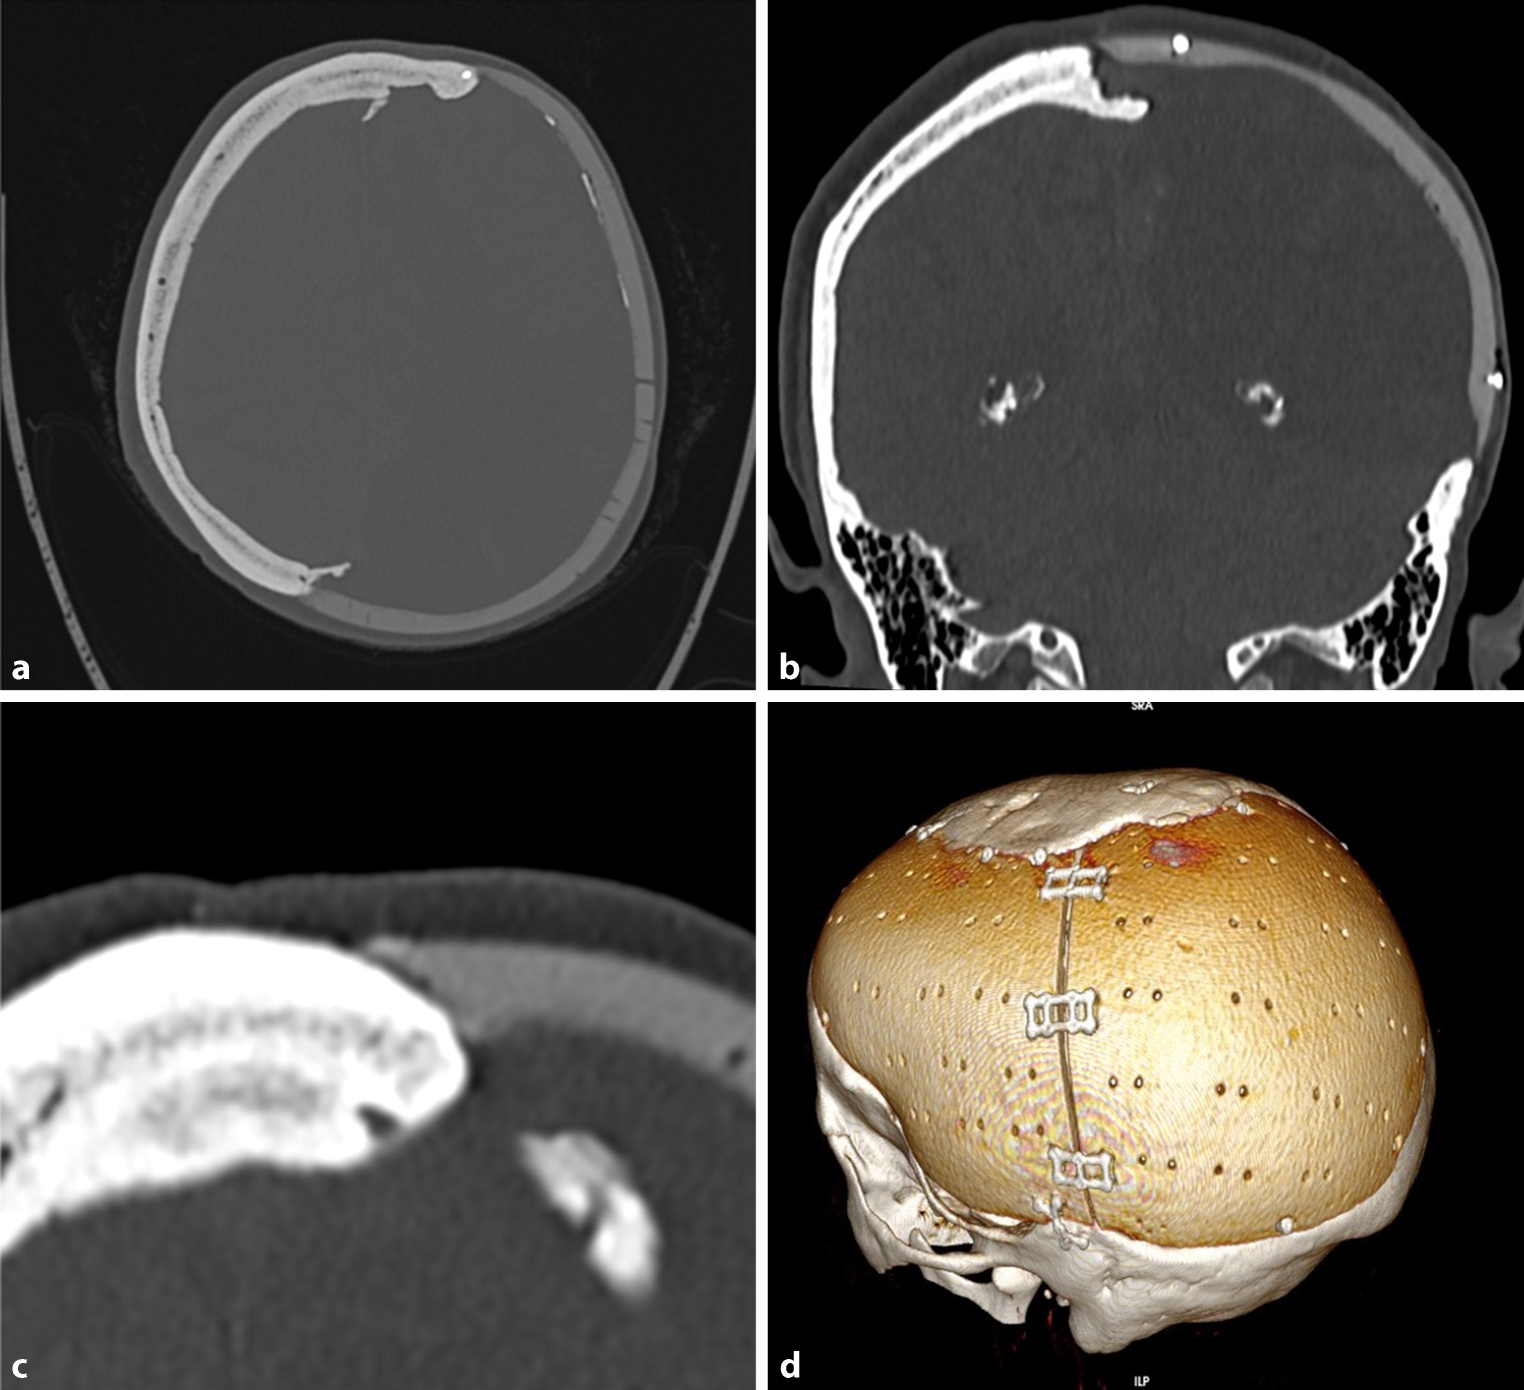

Fig. 7

CT scans of reconstructed calvaria after meningeoma resection, 21 years after reconstruction; a Axial view, calcification of dura; b Coronal view, bone formation under the implant; c Bone-implant contact; d 3‑D image of the 2 implant pieces

The fit of the implant was satisfactory (Fig. 2 and 7) and preserved over more than 20 years as the measurements of the maximum bone-implant distance show (mean 1.88 mm). There were no signs of implant loosening clinically or in the CT. All osteosynthesis material was tightly fixed to the implant and bone. There was no screw that showed a prominence into the intracranial space and no dura involvement. Therefore, the primary measurements for the screws were correct and there was no bone resorption round the osteosynthesis material or adjacent to the implant. This is also due to the possible preoperative planning of the screw length.

The dura showed calcification under the implant in 6 of 9 cases (Fig. 2).

The size of the implants varied from 14.85 cm2 to 451 cm2 (Figs. 8 and 7), with a mean of 116.3 cm2. The implant with the maximum size was inserted in 2 parts and crossed the midline (Fig. 7). Generally, the proper form could be achieved through the preoperative planning including mirroring technique. In none of the cases was it necessary to cancel the surgery because of an incorrect fit of the implant. As these reconstructions were done in major defects, the proper form would be very difficult to achieve with any material formed during surgery.